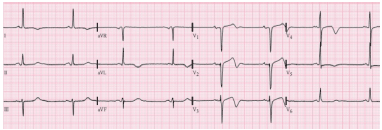

Paciente de 70 anos, sexo masculino, sem comorbidades conhecidas foi admitido no pronto-socorro há 6 horas, com quadro de dor torácica anginosa.

No momento, não apresenta qualquer queixa de dor e está assintomático, sem quaisquer alterações de sinais vitais. Realizou exames de troponina seriados, todos negativos. Segue eletrocardiograma admissional:

Assinale a opção que indica a conduta mais adequada.